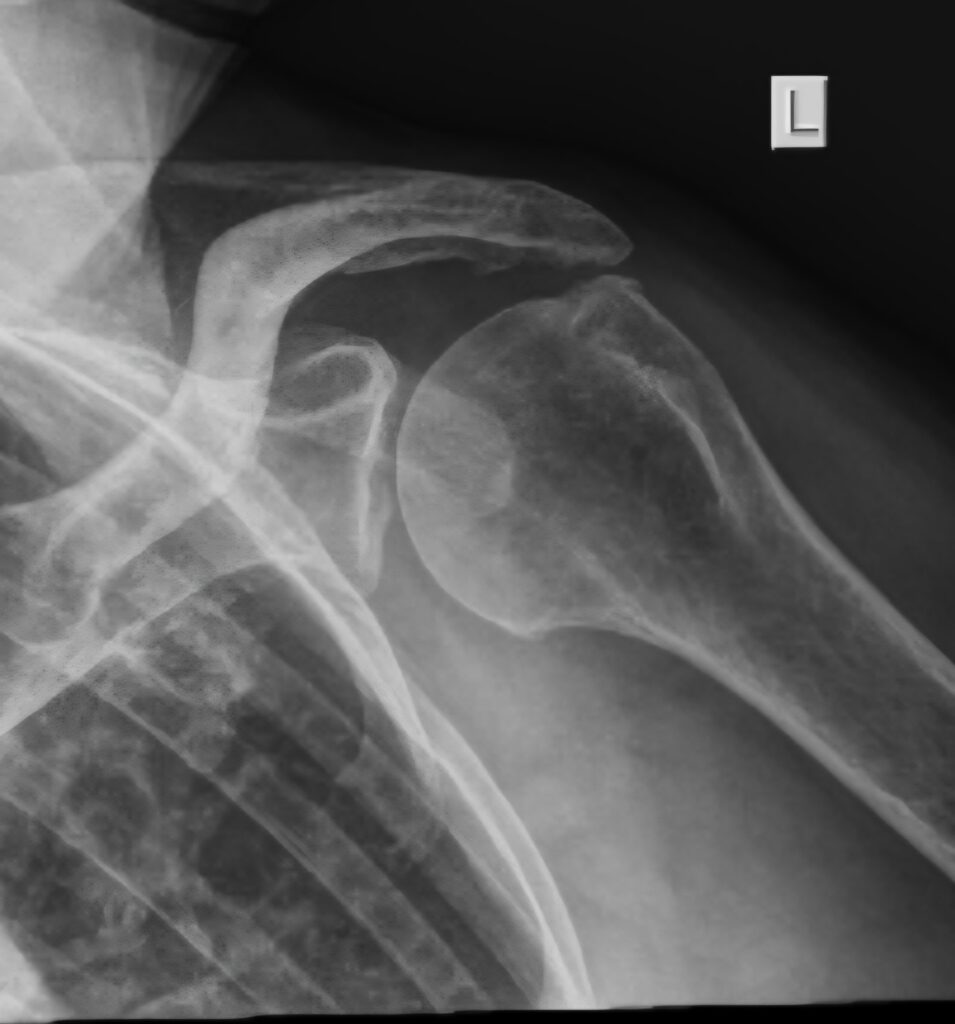

REVERSE TOTAL SHOULDER REPLACEMENT

The rotator cuff is responsible for centering the humeral head in the glenoid and to initiate movement of the shoulder. After initiation the movement is powered by large muscles like the Deltoid and the Pec major etc. If the cuff is torn the first prize is a proper repair , but in patients older than 75 the outcomes are poor. In this patient group there is an alternative, namely a reverse total shoulder replacement. By reversing the ball and socket from the anatomical arrangement, the Deltoid muscle is able to initiate and complete motion of the shoulder. This is and excellent answer to a sticky problem. Not a good option for young patients though